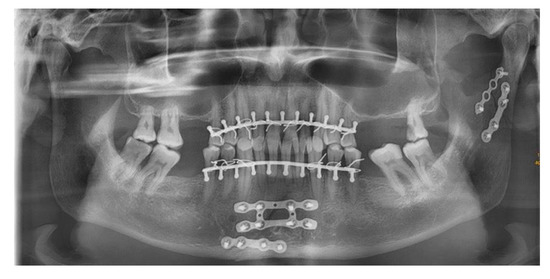

Application of the Plates